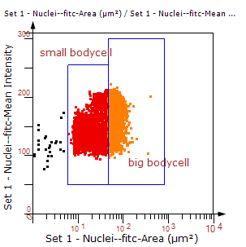

3. 根据FITC通道识别神经胞体并筛选出有效细胞胞体(细胞核识别算法)。

根据染色强度,染色面积,细胞形态学,利用正反向回溯功能和设门圈选Gating,排除杂质,细胞碎片,黏连细胞(绿色框线标记),获得有效的神经元胞体,(粉色框线标记),并将胞体按照面积分为两类(散点图)。

由于该视网膜样本是标记的小胶质细胞,根据面积将神经胞体分为两类(Small bodycell,Big bodycell),反向回溯Big bodycell中的细胞后,应用Input Gate功能筛选短粗的神经纤维,作为激活态的小胶质细胞。